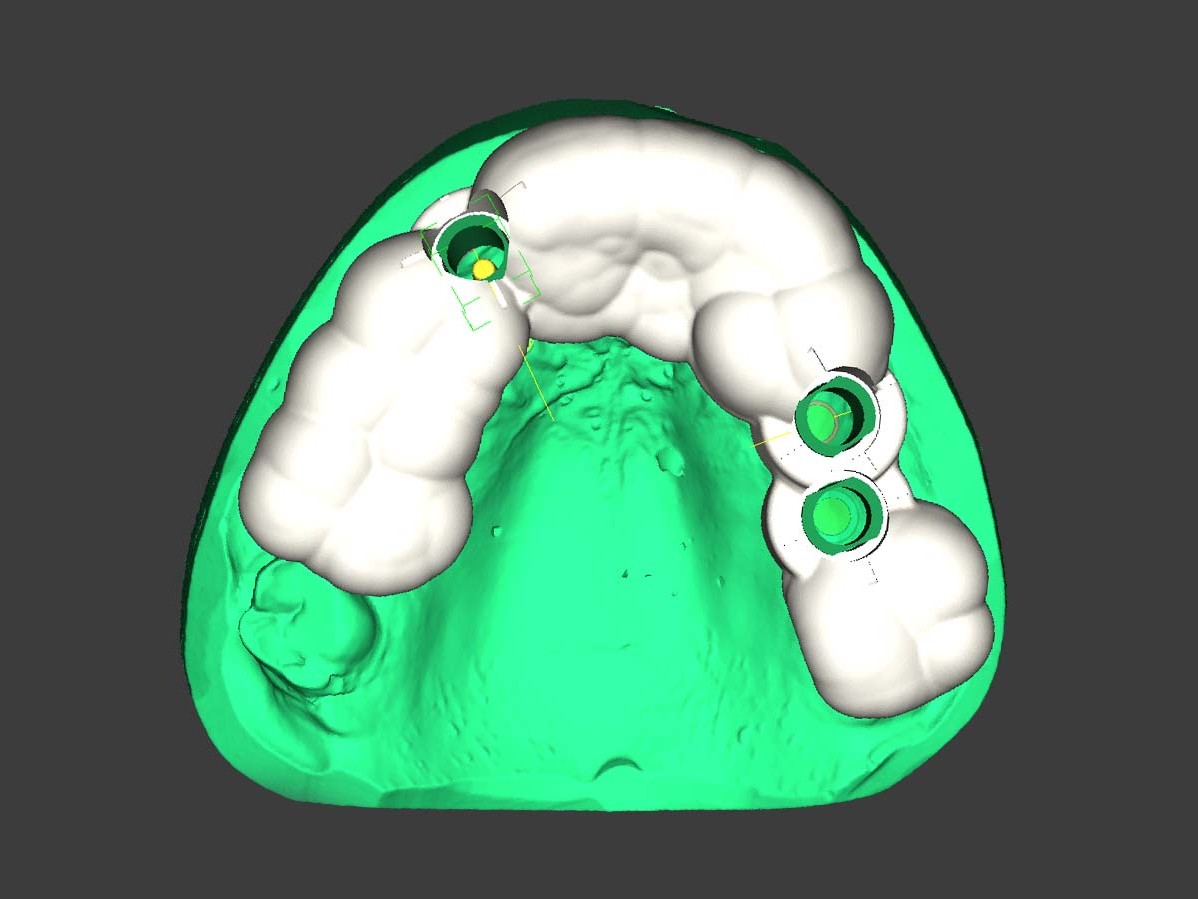

Nach der Erstellung eines DVTs folgte die Konvertierung und Segmentierung der DICOM-Datensätze mithilfe der coDiagnostiX™-Software (Dental Wings GmbH, Deutschland). In diesem Zuge erfolgte die Planung der drei Implantate. In Regio 12 erfolgte die Planung eines Straumann PURE Ceramic Implantat (Ø 3,3 mm, Länge 12 mm). In Regio 25 wurde ein Straumann Bone Level Roxolid Implantat (Ø 4,1 mm, Länge 12 mm) als Sofortimplantation geplant. In Regio 26 wurde ein Straumann Bone Level Roxolid Implantat (Ø 4,1 mm, Länge 8mm) vorgesehen, das über einen CHB-Knochenring zur Augmentation des vestibulären Knochendefizits inseriert werden sollte. Nach der erstellten Planung wurde der Datensatz aus der coDiagnostiX™-Software direkt über das Modul caseXchange an das zahntechnische Referenzlabor übersandt. Parallel erfolgte eine konventionelle Alginat-Abformung des Oberkiefers. Mithilfe des Optical Scan Moduls wurde dieses konventionelle Situationsmodell der Ausgangssituation digitalisiert, in den Planungsdatensatz eingelesen und die Implantatpositionen unter zahntechnischen Gesichtspunkten verifiziert. Vorteilhaft an der frühzeitigen Einbeziehung des Zahntechnikers ist zu erwähnen, dass die Kombination aus implantatchirurgischer und implantatprothetischer Sichtweise dem Patienten ein ideales Endergebnis garantiert. Darüber hinaus werden sowohl der Mund-, Kiefer- und Gesichtschirurg als auch der Zahntechniker für die wechselseitigen Probleme und Herausforderungen des anderen sensibilisiert. Als Folge entwickelt sich eine echte Zusammenarbeit auf Augenhöhe, die implantologische Behandlungen wesentlich effizienter und vorhersagbarer macht. Nach erneutem Upload auf die CaseXchange Plattform erfolgte die Freigabe durch den Mund-, Kiefer- und Gesichtschirurgen, dem chirurgischen Implantologen. Danach konnte das zahntechnische Referenzlabor mit der Fertigung der Bohrschablone beginnen. Hierzu wurde ein weiterer optischer Scan des nun radierten Situationsmodells angefertigt. Dieser dient als Grundlage für das finale Design der Bohrschablone (Abb. 3). Die Software garantiert hierbei dem Anwender ein hohes Maß an Designfreiheit, Feinabstimmung und Detailarbeit. Neben rein zahn-, knochen oder schleimhautgetragenen Schablonen können auch Kombinationen, wie zahn-knochengetragene Schablonen, erstellt werden. In coDiagnostiX kann der Benutzer nun die fertig erstellte Bohrschablone gegen eine Gebühr als offenen STL-Datensatz exportierten und auf dem von ihm bevorzugten Wege herstellen. Die Herstellung kann inhouse oder extern erfolgen. Als Herstellungstechnik kann das 3-D-Drucken oder Fräsen angewandt werden. In dem hier gezeigten Fall wurde die Bohrschablone im 3-D-Druckverfahren inhouse gefertigt.

Abb 3 Digital konstruierte Bohrschablone

Abb. 3: Digital konstruierte Bohrschablone

Neben dem reinen Exportieren des STL-Datensatzes der Bohrschablone ermöglicht es die Software dem Anwender darüber hinaus, auch alle relevanten Daten für eine provisorische Versorgung des Patienten zu generieren. Somit wird der Zahntechniker befähigt, die Modellsituation inklusive Scanmarker und/oder Platzhaltern auszugeben. Die Wahl zwischen Scanmarker oder Platzhalter richtet sich stets nach dem verwendeten Implantatsystem sowie der zugrunde liegenden Indikation. Bei einteiligen Vollkeramikimplantaten entfällt der Export mittels Scanmarker. Um sicherzustellen, dass das präfabrizierte Provisorium die belastungsfreie Einheilung des Straumann PURE Ceramic Implantates gewährleistet, erfolgte der Export der Implantatposition mittels Platzhalter. Dieser kann in der Software frei erstellt werden. In der Standardkonfiguration entspricht der Platzhalter den Geometrien des jeweiligen Implantates exakt. Für die provisorische Versorgung von Keramikimplantaten empfiehlt es sich, bereits in diesem Arbeitsschritt den Platzhalter in Höhe und Durchmesser so zu modifizieren, dass das Provisorium über ausreichend Abstand verfügt. Die so gewonnenen Datensätze der radierten Modellsituation und des Platzhalters wurden in eine weitere CAD-Software geladen und um die ursprüngliche Modellsituation ergänzt (Abb. 4). Im Anamnesegespräch zeigte sich die Patientin mit der Ästhetik ihrer alten Versorgung weitestgehend zufrieden, sodass diese als Ausgangslage für das Design des Provisoriums verwendet werden konnte. Nachdem das Design der dreigliedrigen provisorischen Versorgung am Computer erstellt war, erfolgte die Fertigung des Provisoriums aus PMMA¹⁵ auf einer fünfachsigen Fräsmaschine (Abb. 5).

Abb 4 radierte und ursprünglichen Modellsituation virtuell überlagert

Abb. 4: Radierte und ursprünglichen Modellsituation virtuell überlagert